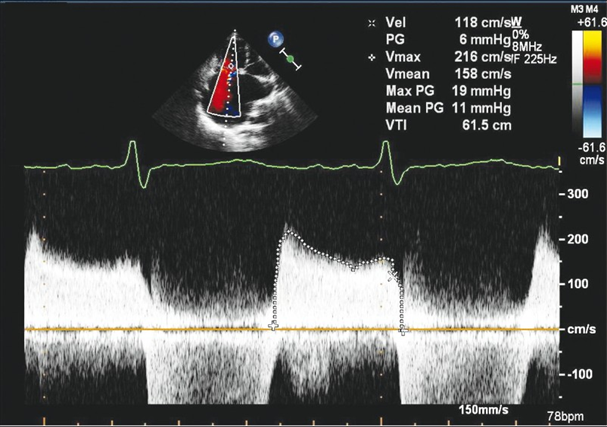

asses in Spectral doppler

Tv Inflow (PW)

RV inflow pattern

PWD gate at tips of TV leaflets

Normal Flow is Antegrade

Use TV package (E/A velocity)

Measure peak E velocity and Decel slope

>1 m/s suggestive of high velocity

2. Measure peak A wave

TV stenosis (CW)

DECREASED E-F SLOPE

OBTAIN TVA USING

PHT METHOD

NORMAL TVA 7-9 CM

TRACE E & A WAVE TO OBTAIN MEAN PG

Severity Scale

Right Ventricular Systolic Pressure (RVSP) is used to

RVSP is used to estimate right side pressures in the vessels leading to the lungs. This is used to determine pulmonary hypertension.

TR Vmax + RAP= RVSP

How to obtain the rsvp/spap

1. Place the CW cursor through the TR color jet

2. Measure the tricuspid regurgitant waveform to achieve the tr velocity

3. The machine will use the TR Vmax velocity and turn it into a pressure gradient. This is done by using the Bernoulli equation

RVSP / Systolic pulmonary artery pressure (SPAP) determined by the TR

TR Max PG + RAP = RVSP/SPAP